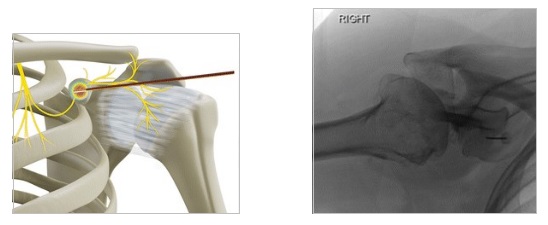

Τι είναι ο φαρμακευτικός αποκλεισμός και η εφαρμογή παλμικής ραδιοσυχνότητας στο υπερπλάτιο νεύρο

Η νευροπάθεια του υπερπλάτιου νεύρου μπορεί να αποτελέσει αιτία επίμονου, διαξιφιστικού πόνου σε ασθενείς με κατάγματα του ώμου και σε αθλητές, όπου μπορεί να παρατηρηθεί τραυματική έλξη του ώμου. Το υπερπλάτιο νεύρο είναι ευάλωτο στη συμπίεση. Το φαρμακευτικό block του νεύρου και ακολούθως η νευρόλυση με χρήση παλμικής ραδιοσυχνότητας, ανακουφίζουν από τον πόνο, χωρίς να χαθεί η κινητικότητα του άνω άκρου. Η διαδικασία νευρόλυσης αποτελεί μια ελάχιστα παρεμβατική πράξη, διενεργούμενη με υπερηχογραφική καθοδήγηση. Οι ασθενείς που έχουν ανταποκριθεί θετικά στον φαρμακευτικό νευρικό αποκλεισμό είναι ιδανικοί υποψήφιοι για την εφαρμογή της θεραπείας αυτής, η οποία θα προσφέρει μακρό σε διάρκεια αποτέλεσμα.

Τι είναι η απονεύρωση του ώμου με θερμοπηξία ή κρυοπηξία

Η οστεοαρθρίτιδα του ώμου αποτελεί αιτία σωματικής αναπηρίας και ψυχικής δυσφορίας. Η μη χειρουργική αντιμετώπιση συχνά δεν είναι σε θέση να αντιμετωπίσει πλήρως τον χρόνιο πόνο στις αρθρώσεις. Επιπλέον, ένας μεγάλος αριθμός ασθενών δεν είναι κατάλληλος για χειρουργική επέμβαση λόγω υποκείμενων σοβαρών προβλημάτων υγείας. Η κατάλυση με ραδιοσυχνότητες (RFA) ή κρυοκατάλυση (cryoablation) των αρθρικών αισθητήριων νευρικών ινών μπορεί να αναστείλει τη μετάδοση των αισθητικών σημάτων πόνου, προσφέροντας έτσι ουσιαστική ανακούφιση. Οι αρθρικοί αισθητικοί κλάδοι του υπερπλάτιου, του μασχαλιαίου και του πλάγιου θωρακικού νεύρου στοχεύονται κατά τη διάρκεια της μεθόδου, οι οποίοι αποτελούν την κύρια πηγή αισθητικής νεύρωσης του ώμου.

Η ελάχιστα επεμβατικές αυτές τεχνικές ενδείκνυνται επίσης, για συμπτωματική ανακούφιση σε ασθενείς που έχουν επίμονο πόνο μετά από χειρουργική επέμβαση αντικατάστασης της άρθρωσης.

Εφαρμόζονται με τοπική αναισθησία σε ξύπνιο ασθενή και κάτω από συνεχή ακτινοσκοπικό έλεγχο.